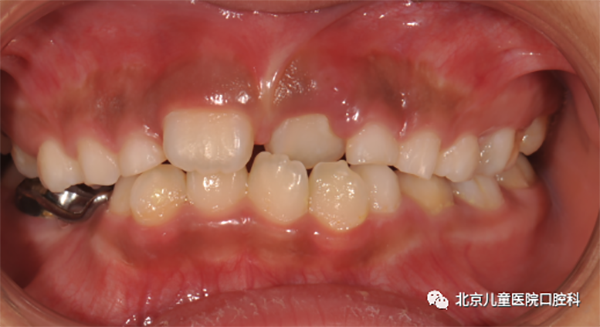

1. 多生牙或埋伏牙

应拔除多生牙或埋伏牙,并利用正畸手段使正中间隙得以闭合。

图1 埋伏牙